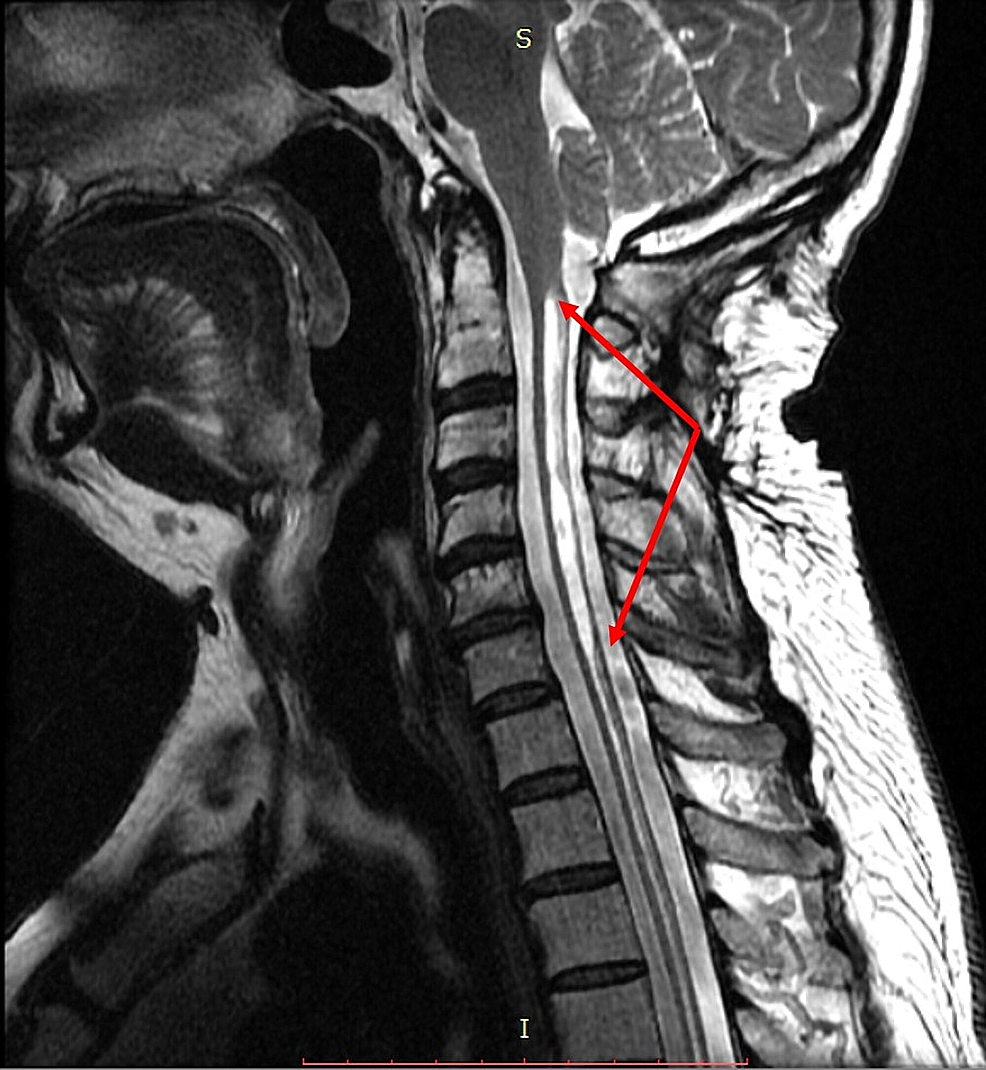

Syrinx Of Spinal Cord Physical Therapy . The goal of surgery is to remove the pressure the syrinx places on the spinal cord and to restore the regular flow of cerebrospinal. People with primary spinal syringomyelia and associated symptoms are often managed conservatively. A case report suggests spinal cord stimulation may be effective for patients with syringomyelia related neuropathic pain 30. Syringomyelia is a condition in which a cyst filled with cerebrospinal fluid (csf) called a syrinx forms within your spinal cord. The cyst, which is sometimes called a syrinx, can grow larger over. 4 the fluid forms a cavity called a syrinx.

The cyst, which is sometimes called a syrinx, can grow larger over. 4 the fluid forms a cavity called a syrinx. People with primary spinal syringomyelia and associated symptoms are often managed conservatively. Syringomyelia is a condition in which a cyst filled with cerebrospinal fluid (csf) called a syrinx forms within your spinal cord. A case report suggests spinal cord stimulation may be effective for patients with syringomyelia related neuropathic pain 30. The goal of surgery is to remove the pressure the syrinx places on the spinal cord and to restore the regular flow of cerebrospinal.